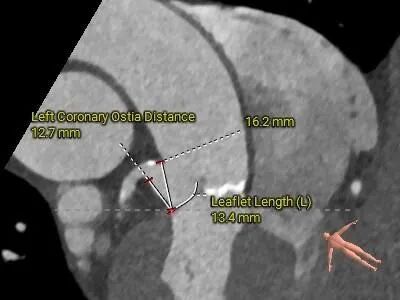

• 左、右冠高度可,切线位测量,左窦瓣叶稍长于左冠开口下缘;左主干及前降支可见部分钙化斑块;

冠脉评估

• 左、右冠高度可,切线位测量,左窦瓣叶稍长于左冠开口下缘,结合瓦氏窦、STJ内径综合预估,冠脉阻挡风险适中,术中在瓣膜释放至工作位后进一步观察冠脉灌注情况;